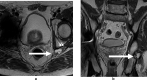

Objective: Acetabular paralabral cysts are common and are almost always associated with labral tears. Uncommonly, they extend into the periacetabular soft tissues or may propagate along peripheral nerves causing pain and hip dysfunction. The aim was to evaluate the clinical and MRI presentations of such cases including perineural propagation.

Results: 14 cases were recorded. The mean age was 56.9 years (range = 30-79 years) and female:male ratio was 1:2.6. The commonest presenting complaint was hip pain (10/14, 71.4%). Other complaints included groin pain, perineal pain and hip dysfunction. No symptoms were attributed to the acetabular paralabral cyst in 3/14 patients (21.4%). None had foot drop. The cysts were multilocular in all cases and were homogenously T2 hyperintense in 13/14 (92.9%). Labral tears were identified in 11/14 cases (78.6%). The sciatic nerve was most commonly involved in 5/14 cases (35.7%) with the obturator, medial femoral cutaneous nerve, femoral nerve, superior and inferior gluteal nerves also affected.No intervention was undertaken in 9/14 cases (64.3%). 5/14 (35.7%) underwent image guided aspiration and corticosteroid injection. 4/5 such patients reported reduced pain following the procedure.